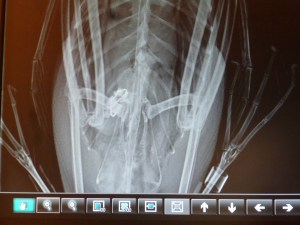

Initial x-rays revealed not just one hook, but two hooks similar to a rig for walleye fishing. One of the hooks had already made its way deep into the proventriculus. The proventriculus is one part of two parts of a bird’s stomach. It has very acidic pH which softens food to make it easier for the bird to digest. There was also a spot on the x-ray which could’ve been a lead sinker or a rock. If it was indeed a lead sinker, the possibility of lead poisoning was highly likely.